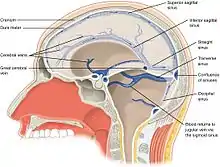

The ventricles are filled with cerebrospinal fluid (CSF) which bathes and cushions the brain and spinal cord within their bony confines. CSF is produced by modified ependymal cells of the choroid plexus found in all components of the ventricular system except for the cerebral aqueduct and the posterior and anterior horns of the lateral ventricles. CSF flows from the lateral ventricles via the interventricular foramina into the third ventricle, and then the fourth ventricle via the cerebral aqueduct in the midbrain. From the fourth ventricle it can pass into the central canal of the spinal cord or into the subarachnoid cisterns via three small foramina: the central median aperture and the two lateral apertures. According to the traditional understanding of cerebrospinal fluid (CSF) physiology, the majority of CSF is produced by the choroid plexus, circulates through the ventricles, the cisterns, and the subarachnoid space to be absorbed into the blood by the arachnoid villi.

The fluid then flows around the superior sagittal sinus to be reabsorbed via the arachnoid granulations (or arachnoid villi) into the venous sinuses, after which it passes through the jugular vein and major venous system. CSF within the spinal cord can flow all the way down to the lumbar cistern at the end of the cord around the cauda equina where lumbar punctures are performed.

The four cavities of the human brain are called ventricles.[6] The two largest are the lateral ventricles in the cerebrum, the third ventricle is in the diencephalon of the forebrain between the right and left thalamus, and the fourth ventricle is located at the back of the pons and upper half of the medulla oblongata of the hindbrain. The ventricles are concerned with the production and circulation of cerebrospinal fluid.[7]